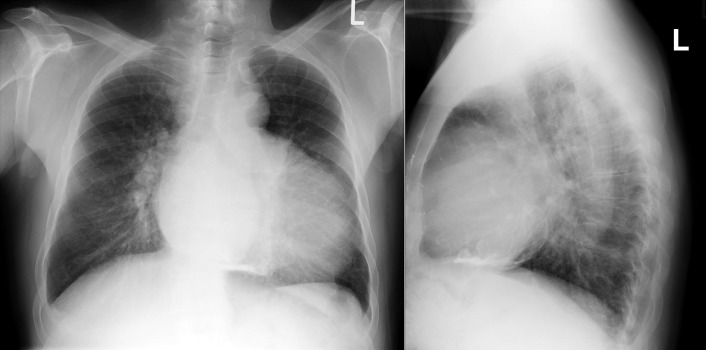

In constrictive pericarditis ( Graphic 16-1 ; Figs. 16-16 to 16-23 ) , the CPS is usually nonspecifically and mildly enlarged. Occasionally, the heart is normal or small in size. The left atrium is the most frequently enlarged chamber, because its enlargement is less restricted by pericardium. The right atrial contour on the frontal chest radiograph may be flattened. Calcification of the pericardium suggests past tuberculosis, but since tuberculosis has become uncommon at most centers, 90% of cases of constrictive pericarditis are currently noncalcified. Calcification, especially diaphragmatic, is not specific for constrictive physiology; it may be seen in the absence of cardiac compression. The apical surface is less frequently calcified than the interventricular and atrioventricular grooves. The apex seldom calcifies prominently in constrictive pericarditis; this finding suggests a calcified apical aneurysm rather that constrictive pericarditis.